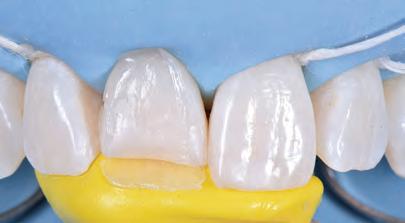

On the day of treatment, following local plexus anaesthesia, UR1 was isolated using a rubber dam, extending the isolation to the first premolars (Figure 4).

In order to correct the altered passive eruption, it was decided to recreate the emergence profile of the tooth by accentuating the vestibular bulge and seeking symmetry with the contralateral element. For this purpose, a pre-formed metal matrix was used and was blocked with two wedges. Once the matrix had been adapted, the adhesion procedures were carried out with a three-step etch and

FIGURE 5: Removal of fractured composite restoration.

FIGURE 6: Use of matrix and adhesion with three-step etch&rinse system.